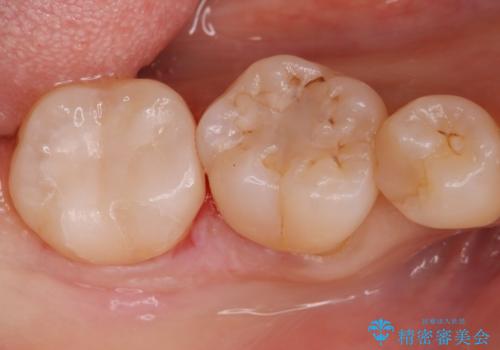

虫歯により歯が欠けていたので拡大鏡下で虫歯を除去した後、セラミックの詰め物で治療しました。

- e-maxインレー 7.7万円 費用は治療当時の料金となります

適合の良い詰め物が入りました。

セラミックスは虫歯の再発のリスクが低くなります。